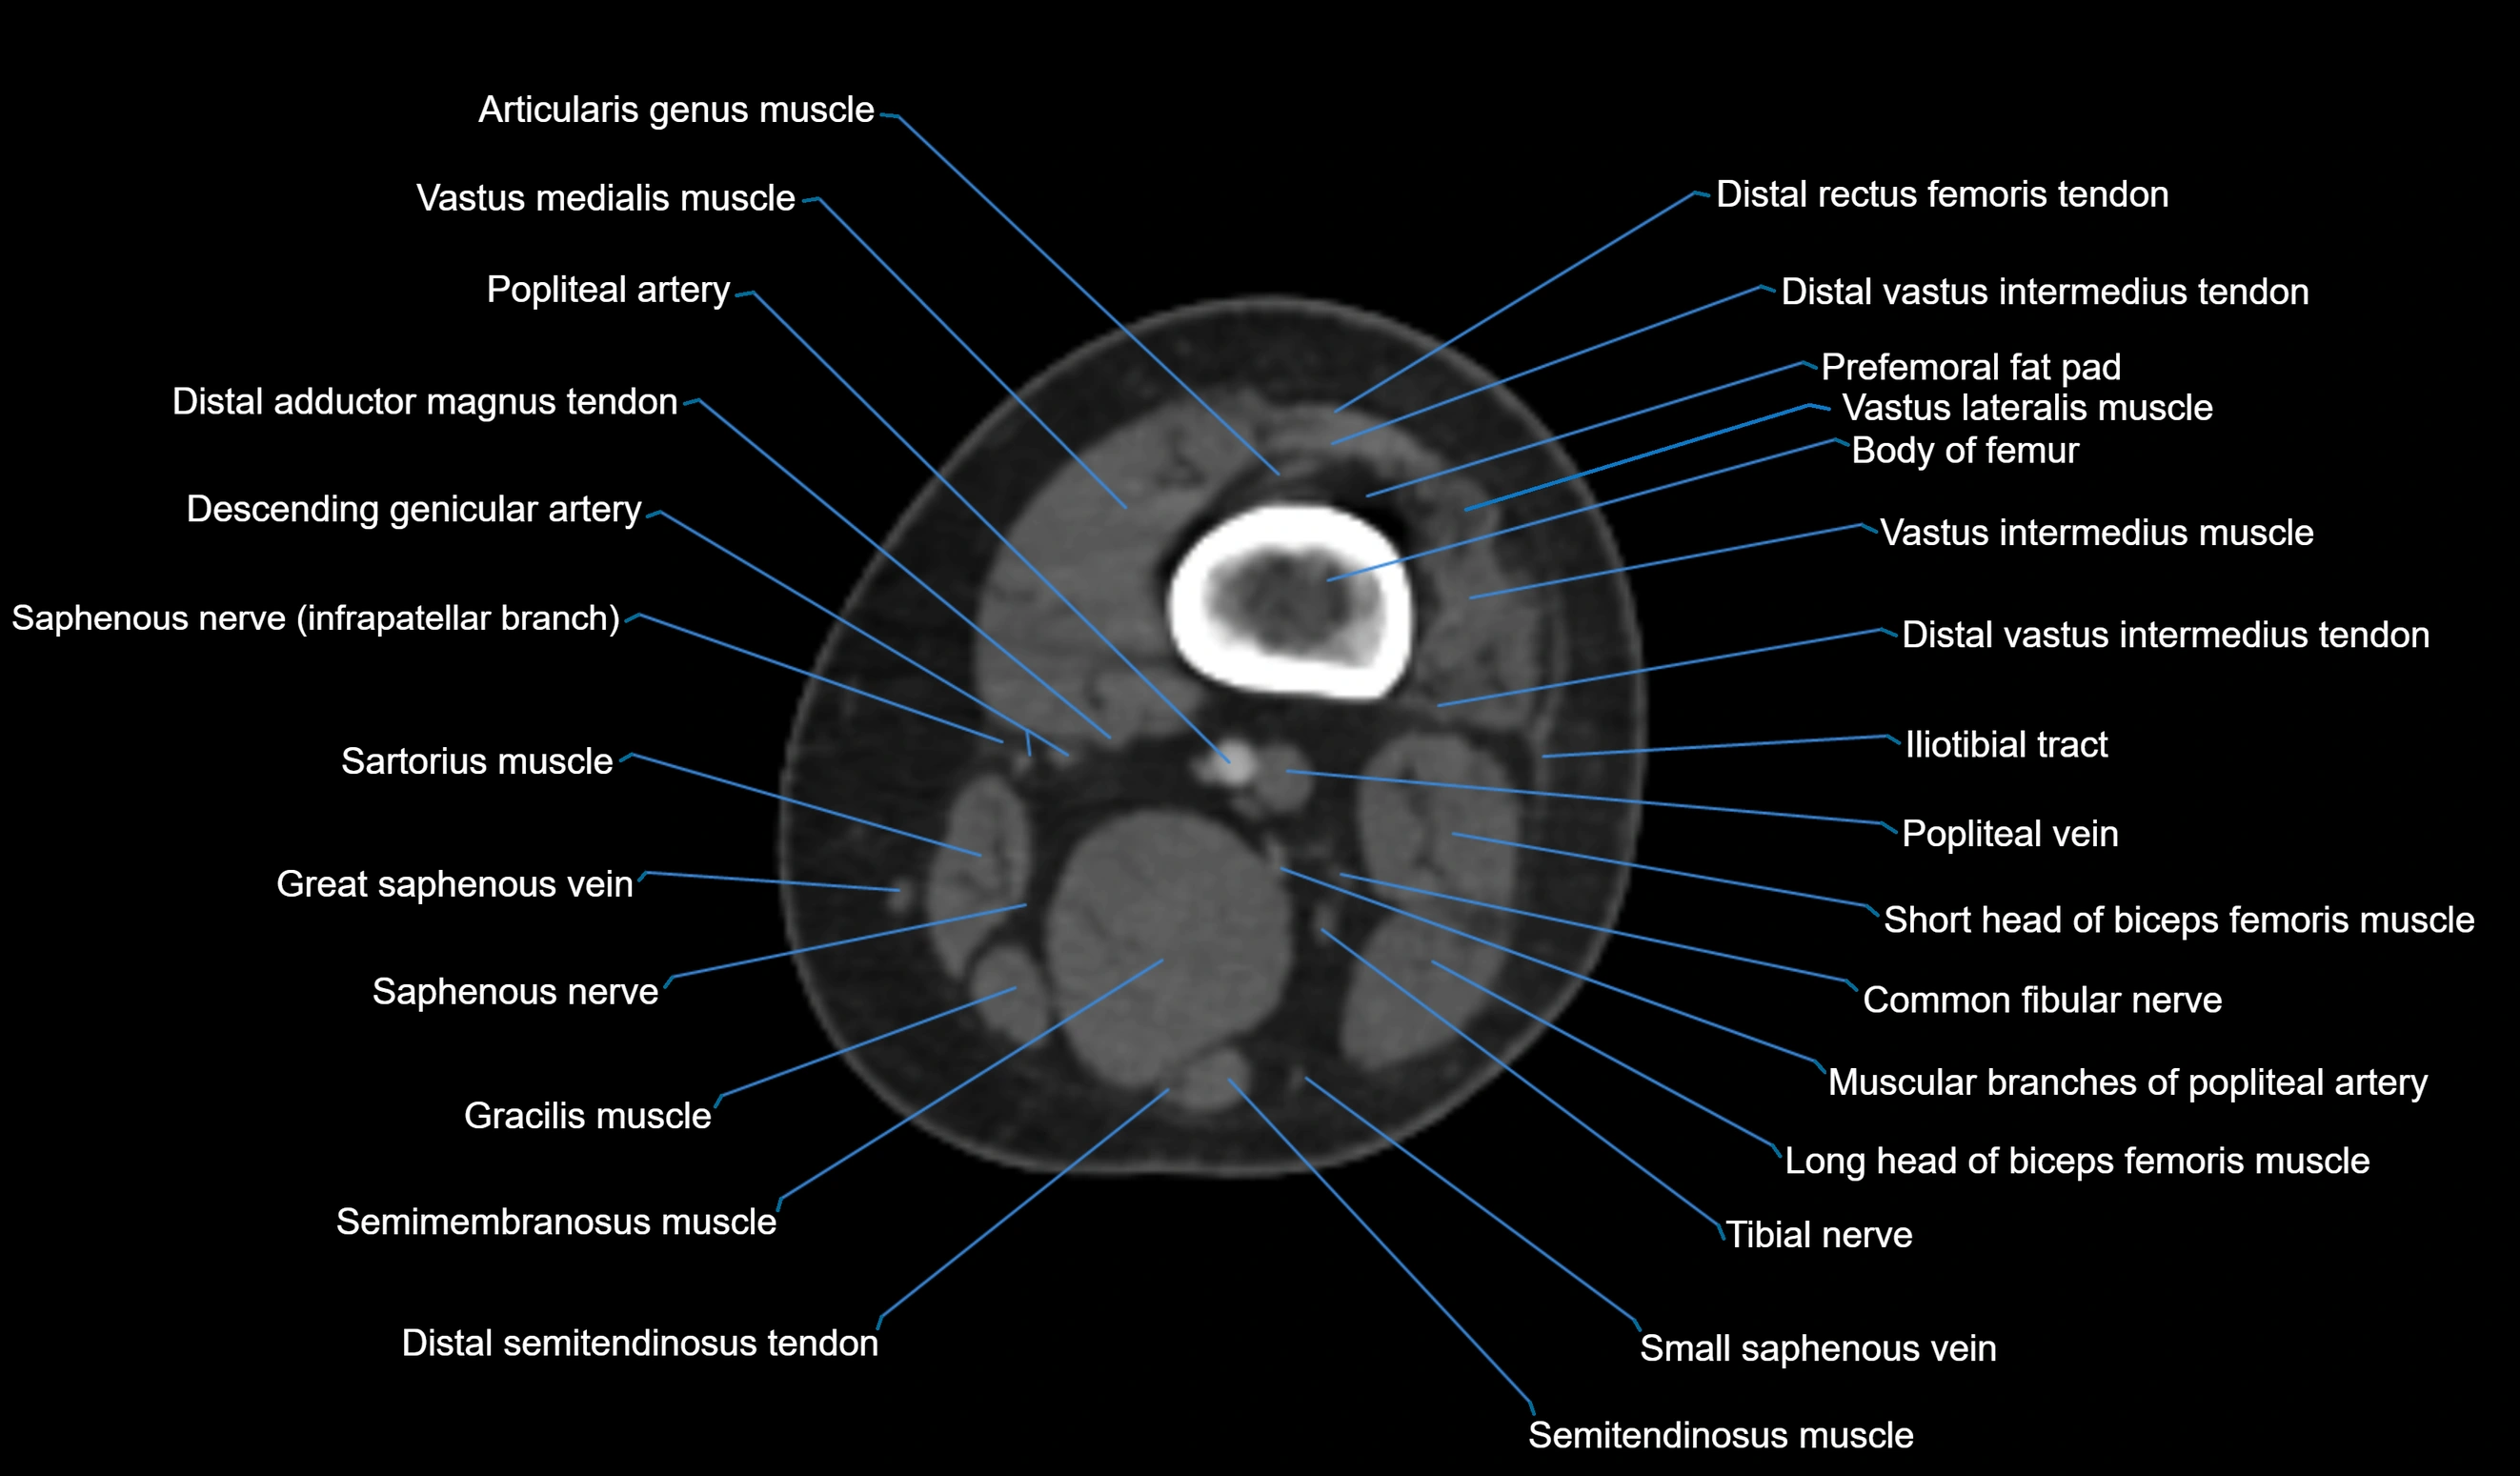

- Body of femur

- Common fibular nerve

- Distal adductor magnus tendon

- Distal rectus femoris tendon

- Distal vastus intermedius tendon

- Popliteal artery

- Popliteal vein

- Prefemoral fat pad

- Saphenous nerve

- Sartorius muscle

- Semitendinosus muscle

- Tibial nerve

- Vastus lateralis muscle

- Vastus medialis muscle